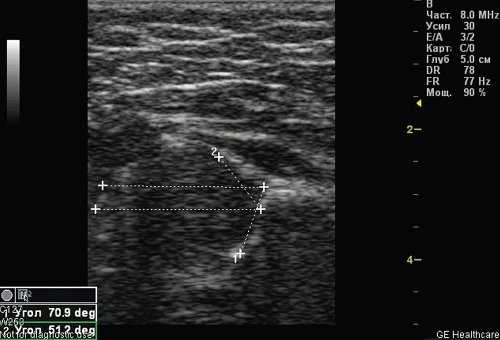

По результатам УЗИ у 286 (72,41%) детей диагностированы типы 1а и 1б тазобедренных суставов (по Г. Рейнгарду). Клинически и сонографически типы 1а и 1б соответствуют возрасту ребенка - это здоровые суставы. Костная часть вертлужной впадины хорошо определяется, костный эркер слегка сглажен или прямоугольный, хрящевая часть крыши охватывает головку бедренной кости, костно-хрящевое соотношение больше или равно 2/3. Угол α больше или равен 60°. Угол β меньше 55° - тип 1а (рис. 1); угол β больше 55° - тип 1б.

Рис. 1. Тазобедренный сустав тип 1а.

1 - угол α=70,9°;

2 - угол β=51,2°.